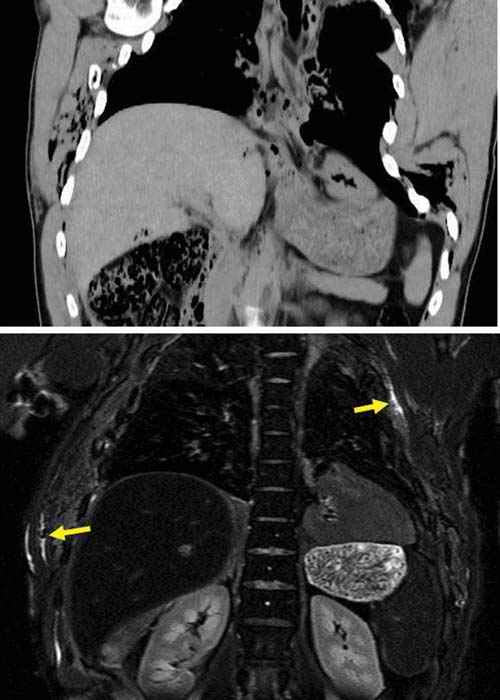

![]() |

In cases of strangling or throttling, a limited amount of pressure is exerted onto the cervical vessels, thus giving rise to petechial hemorrhages. However, they are rarely encountered in cases of classic suicidal hanging. In these cases, the afferent and efferent blood vessels to the head are typically-if the noose is behind the mandibular angle-equally compressed. Therefore, no petechial hemorrhages are to be expected. Here, a thorough medicolegal inspection can reveal telltale imprints to the neck, even if the noose has been removed. Slight and superficial abrasions of the skin can often lead to the correct diagnosis. Additional hemorrhages of the subcutaneous tissue and the cervical musculature can, according to our experience, further support this hypothesis (Figure D3.2.18), although recent literature is uncertain as to the overall significance [17,18]. Furthermore, fractures of the hyoid bone or thyroid horns, a finding easily detected in postmortem MSCT (Figure D3.2.19 and Figure D3.2.20), give rise to the diagnosis blunt trauma to the neck [19,20].

These situations, when faced by inexperienced or all too experienced colleagues, can give rise to the premature diagnosis suicide by hanging. Unfortunately, it cannot be stressed enough that scene findings, no matter how convenient they may be, should always be seen in a critical light in the context as a whole. If only a single finding does not fit into the whole scene, then the examination should be performed with even more ardor and scrutiny than usual. The question of a homicide by prior choking and subsequent hanging to imitate a suicidal hanging must always be addressed [21]. Apart from the crime scene investigation, the medicolegal examination is of utmost importance. Here, several techniques, such as the assessment of muscle histology [22], can be of assistance. As Aghayev et al. [23] show, the examination of the posterior cricoarytenoid muscle can serve as an imminently important finding in cases of suspected blunt trauma to the neck such as in choking.

Postmortem imaging, especially in the form of MRI, can visualize such lesions that would otherwise only be detected at autopsy. The pathology and forensic imaging of choking is dealt with in further detail in Chapter D3.7, "Strangulation." Obviously, osseous lesions are easily seen in postmortem MSCT. Hyoid and thyroid fractures can give clues as to whether a blunt trauma occurred to the neck. A caveat is nevertheless to be made: Anatomical variations of the thyroid and hyoid structures may give the impression of such violent injuries. In these cases, a surrounding hemorrhage-as found in traditional autopsies-must be looked for. The lack of such hemorrhages in postmortem imaging deems a vital or fresh fracture of the throat skeleton rather unlikely.